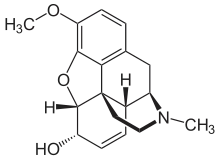

- Esters of morphine opiates: slightly chemically altered but more natural than the semi-synthetics, as most are morphine prodrugs, diacetylmorphine (morphine diacetate; heroin), nicomorphine (morphine dinicotinate), dipropanoylmorphine (morphine dipropionate), desomorphine, acetylpropionylmorphine, dibenzoylmorphine, diacetyldihydromorphine;[261][262]

- Semi-synthetic opioids: created from either the natural opiates or morphine esters, such as hydromorphone, hydrocodone, oxycodone, oxymorphone, ethylmorphine and buprenorphine;